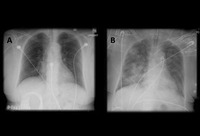

Acute aspiration

Barium aspiration. A barium swallow was conducted in a 53-year-old woman. Imaging revealed hyperdense airway-centered material in the left lower lobe consistent with barium aspiration bronchiolitis. A tracheoesophageal fistula was confirmed

From the collection of Dr Augustine Lee; used with permission of Mayo Foundation for Medical Education and Research, all rights reserved